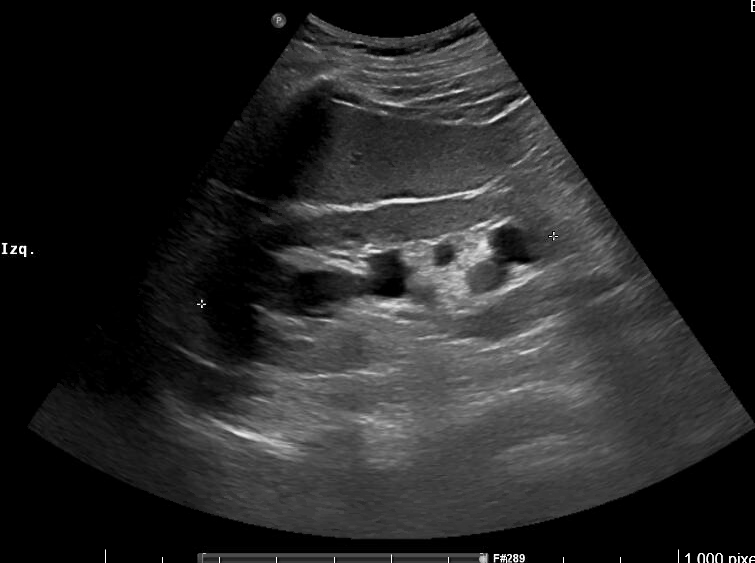

Imágenes 2 y 3. Riñón izquierdo: hidronefrosis grado II. Disminución del grosor cortical. Tamaño 11.5 cm.